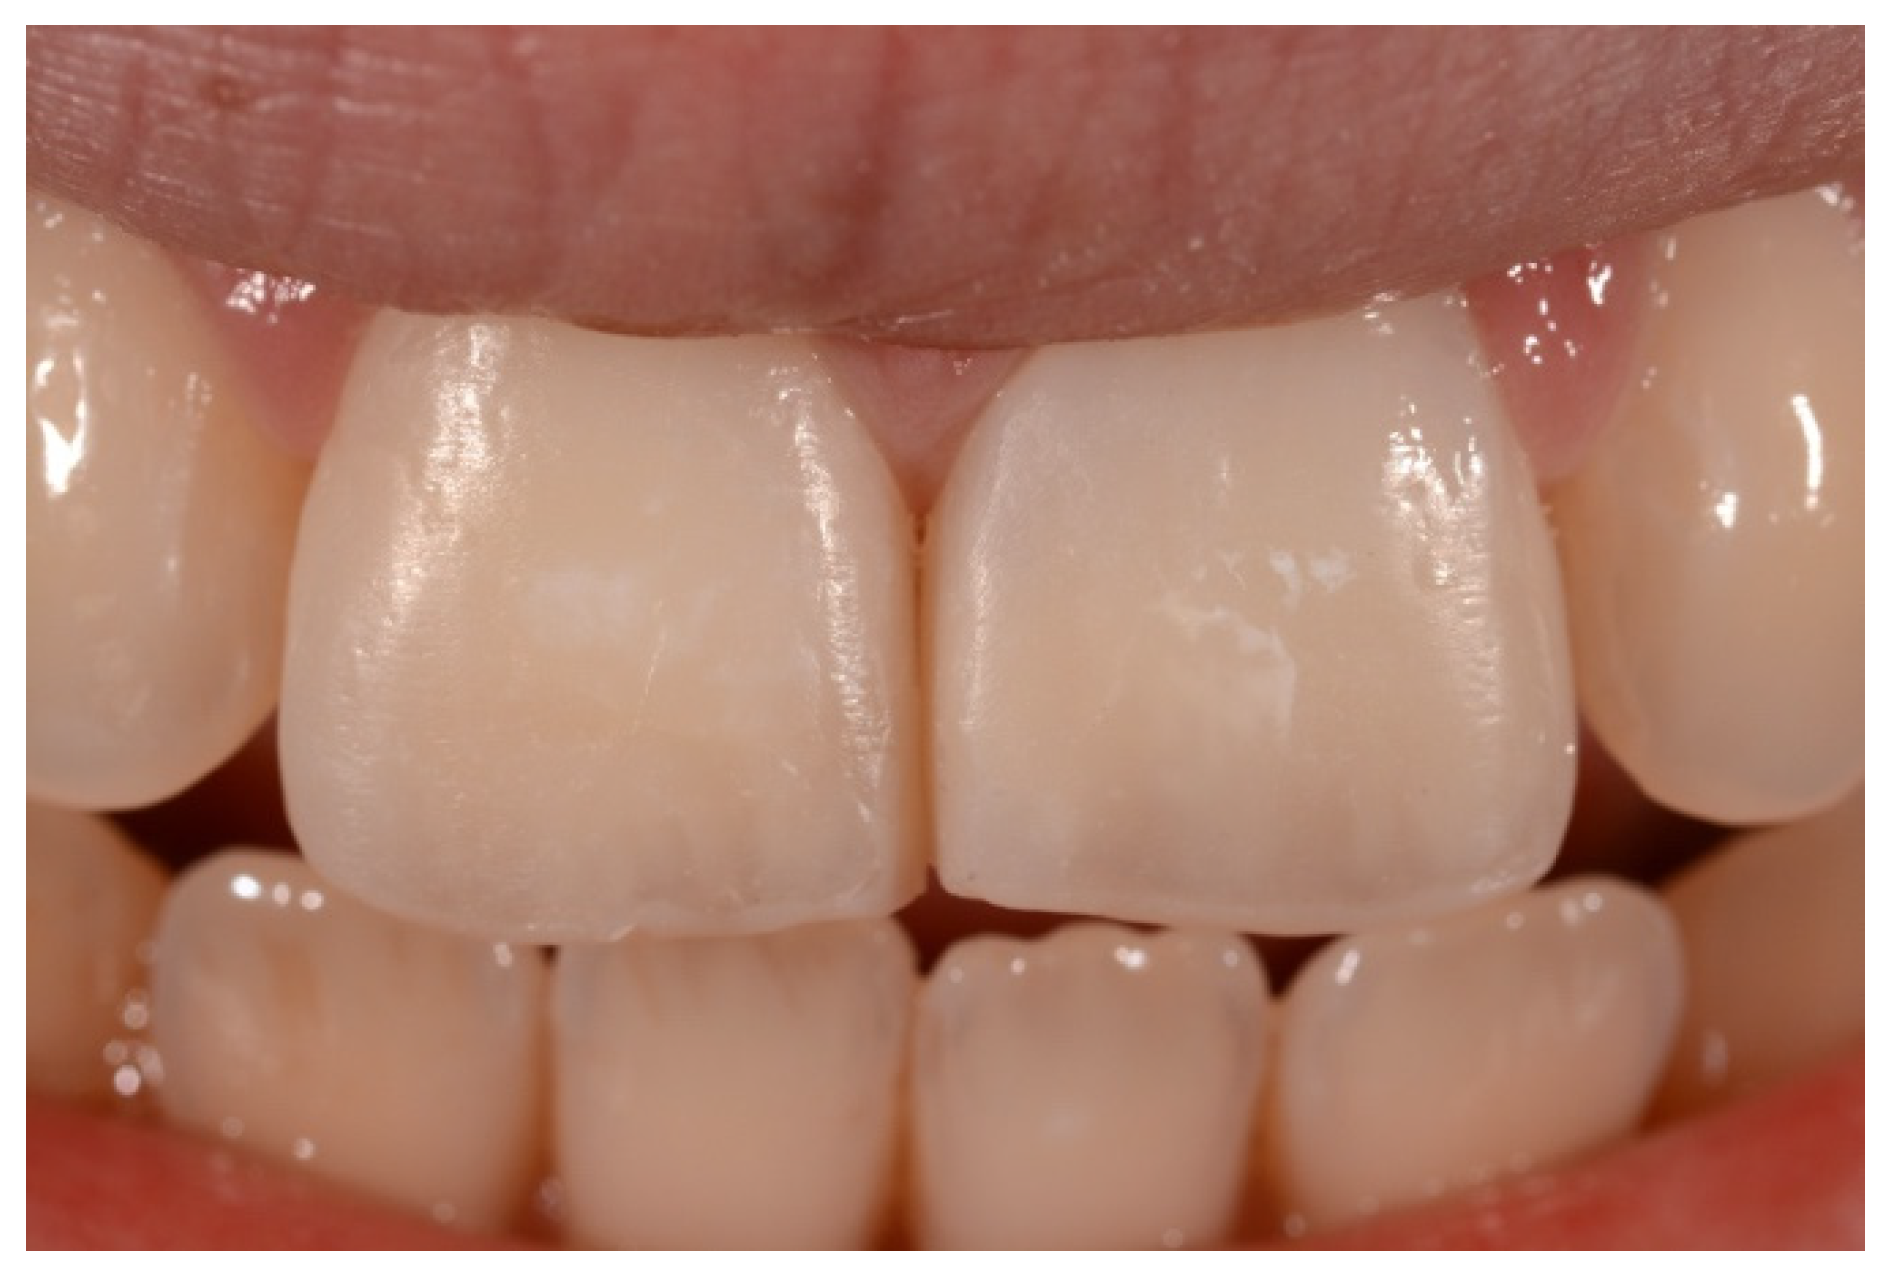

2. Case Presentation

- Molding palatal wall and incisal margin;

- Building interproximal walls with matrices;

- Layering free-hand buccal surface.